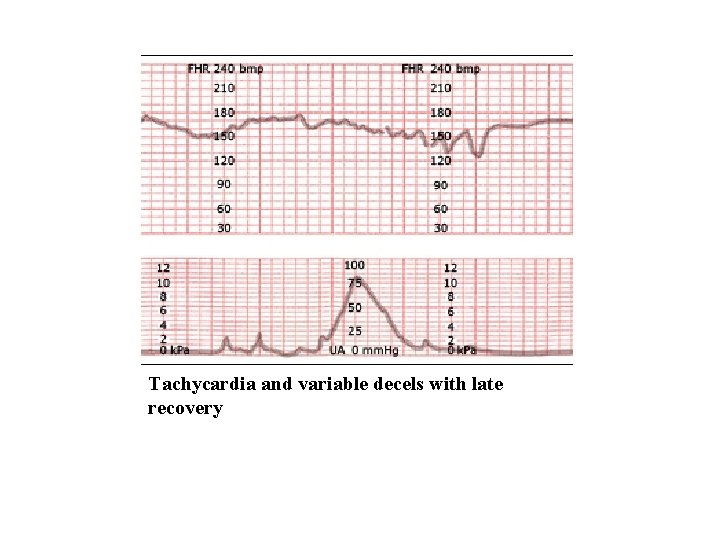

Tachycardia and variable decels with late recovery